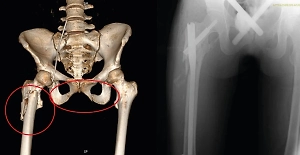

В Нижегородской области 63-летний мужчина случайно отрубил себе кисть во время работ с циркулярной пилой. Врачи местной больницы смогли спасти конечность, сообщает телеграм-канал Ni Mash.

Как сообщил сын пострадавшего, кисть «буквально висела на коже» после несчастного случая. Травматологи в ходе трёхчасовой операции восстановили кровоснабжение и сшили повреждённые сухожилия, нервы и сосуды.